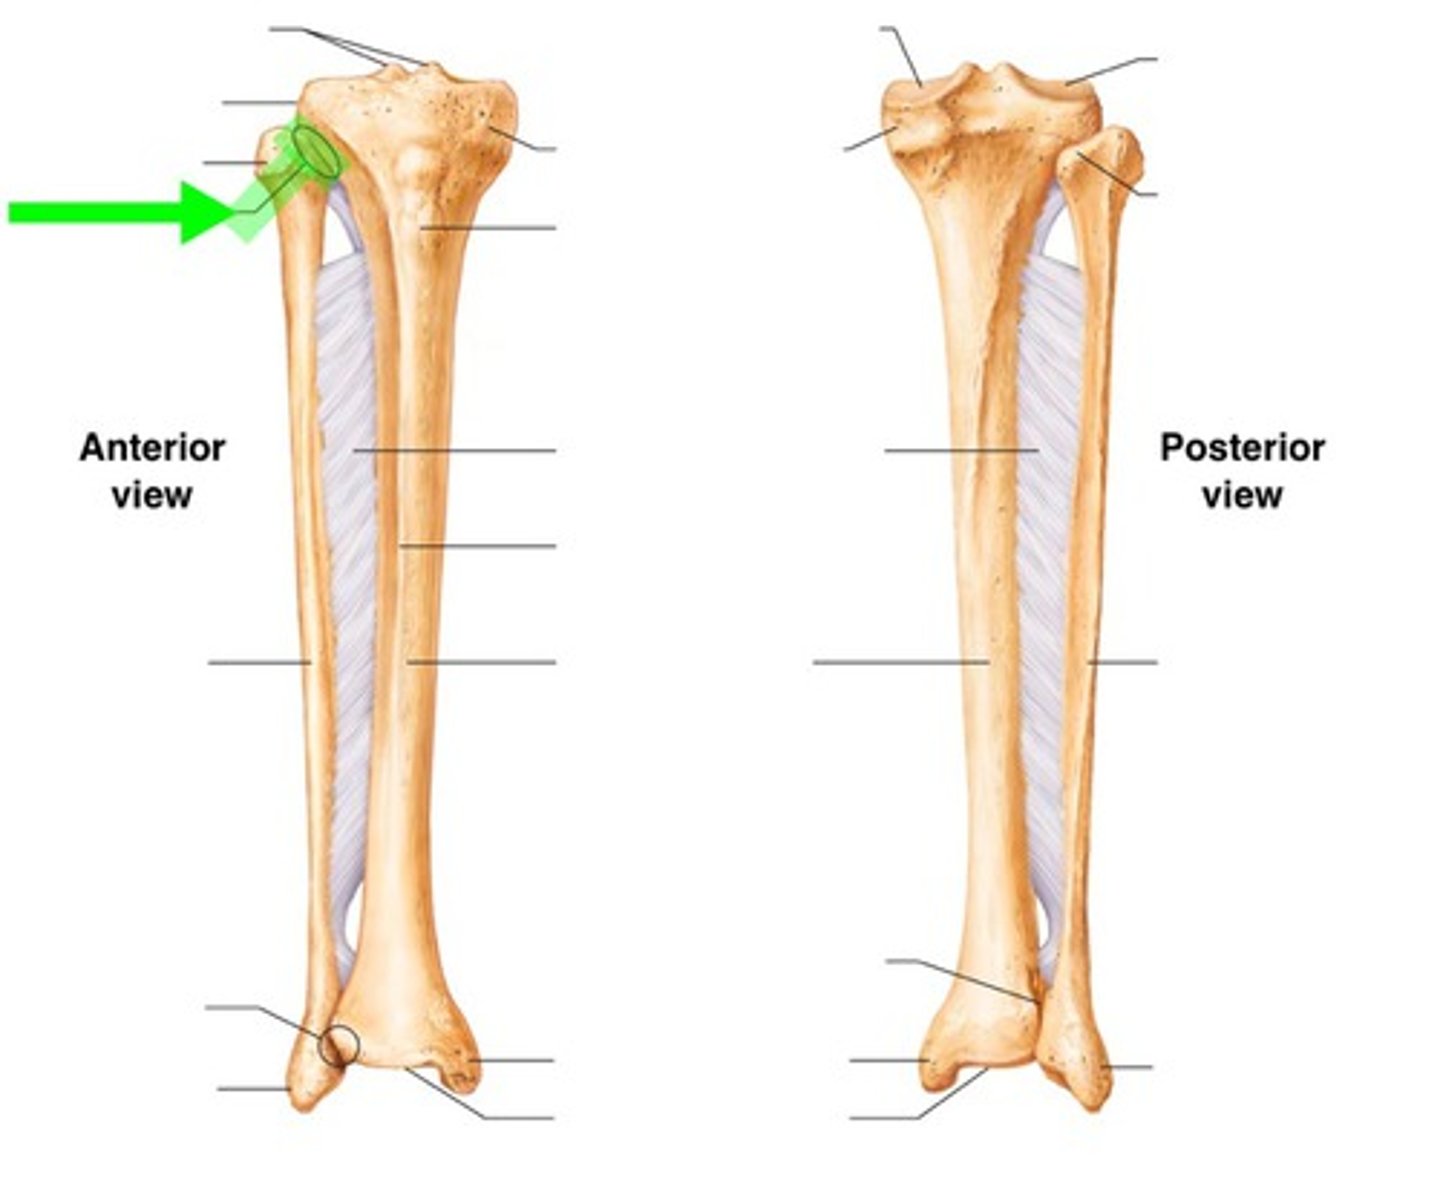

Joint classification of the proximal tibiofibular joint

Synovial joint (2 flat or slightly oval surfaces)

Movement allowed at proximal tibiofibular joint

Little gliding movement

Stability for the proximal tibiofibular joint is provided by... (3 structures)

Ligaments

Joint capsule

Popliteus tendon

Joint classification of the distal tibiofibular joint

Synarthrodial joint

How much movement is allowed at the distal tibiofibular joint?

Minimal movement

Stability for the distal tibiofibular joint is provided by... (3 structures)

Interosseous ligament

Anterior tibiofibular ligament

Posterior tibiofibular ligament